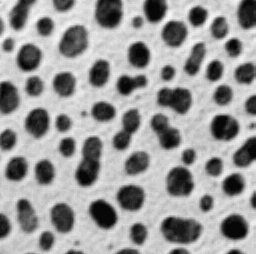

*some droopy things*